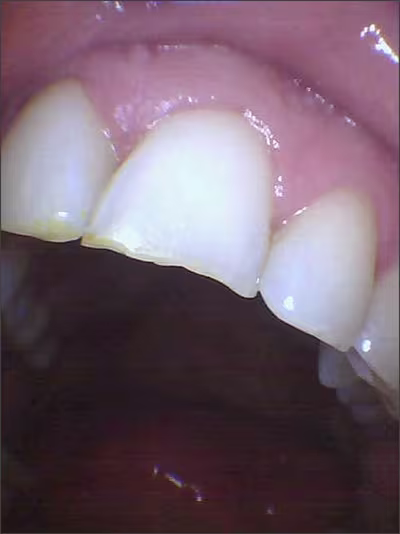

Putting a constant amount of force on the enamel weakens the area and can contribute to small fractures, which lead to chips and breaks.7 As teeth wear, the edges of the anterior teeth and the cusps or corners of the posterior teeth will begin to show micro-fractures or cracks, which usually cannot be seen on radiographic images (Figures 5‑6). Sometimes patients think these fractures are cavities because they can become stained or discolored and may be sensitive to hot and/or cold. As these fractures deepen to the constant pressure, they will eventually chip, break a corner, or damage the pulp requiring endodontic (root canal) therapy. In extreme cases the tooth may need to be extracted. The fracture begins on the outer surface of the tooth and eventually deepens until the crack enters the nerve, which leads into cracked tooth syndrome–an etiology of bruxism.21,39

Figure 5.

Jagged, chipped and thinning enamel on the incisal edge.

Figure 6.

#9 – small chips

#10 – flat, smooth incisal